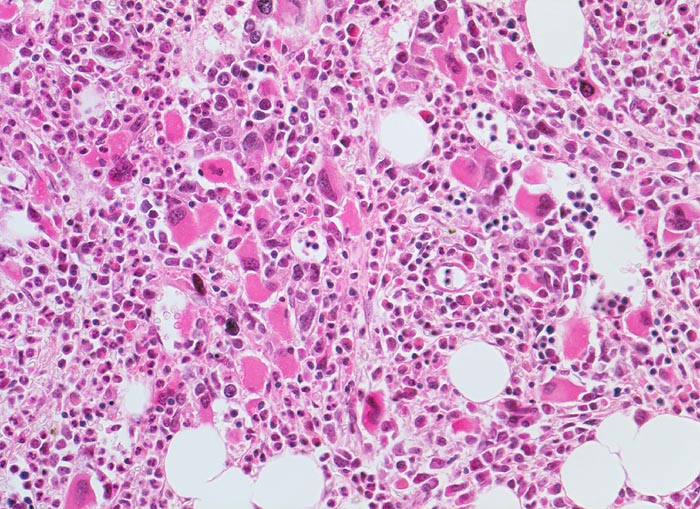

Primäre Myelofibrose (PMF)

Knochenmark, Beckenkamm

Vermehrung von atypischen in Gruppen liegenden Megakaryozyten in perisinusoidaler Position. Typisch ist die intravasale Hämopoese in dilatierten Sinusoiden. Hyperplasie von ausreifenden Granulozyten. Erythropoese hypoplastisch. Durch die Fibrose entsteht der Eindruck von strömenden Zellen.

Die Megakaryozyten sind bei der primären Myelofibrose deutlich vermehrt und bilden oftmals Haufen. Sie zeigen eine deutliche Reifungsstörung mit hypolobulierten chromatindichten Kernen und Grössen zwischen Riesen- und Mikroformen (nackte Megakaryozytenkerne ohne Zytoplasma).